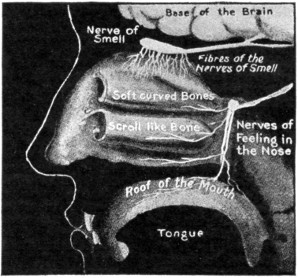

ITS STRUCTURE—ORGANIZATION INTO SYSTEMS—FUNCTIONS—SPECIAL SENSES—NERVOUS SYSTEM—PERSONAL HYGIENE—PREVENTION OF DISEASE—INTERDEPENDENCE OF BODY AND MIND—EUGENICS—ILLUSTRATIONS AND CHARTS.